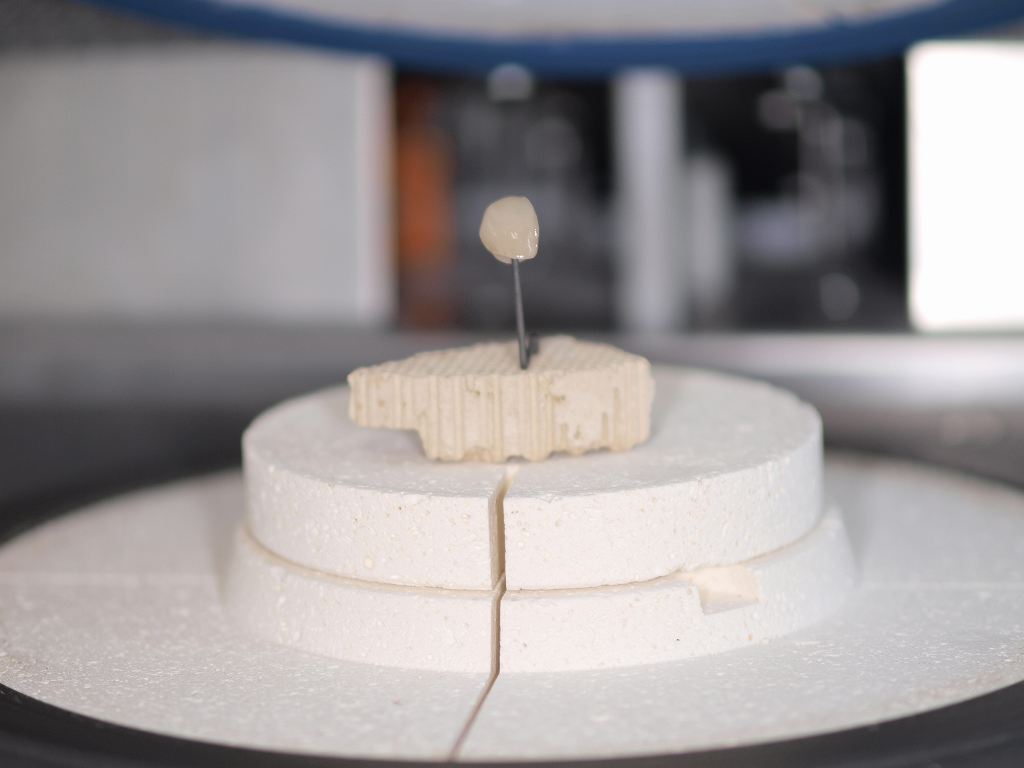

前歯部の作成はジルコニアフレームを使ったジルコニアクラウンというやり方とe-maxを使ったオールセラミッククラウンというやり方に分かれます。 強度はジルコニアフレームの方がありますが、複雑な工程を要しますので費用は2万円高く8万円となります。

前歯部の作成はジルコニアフレームを使ったジルコニアクラウンというやり方とe-maxを使ったオールセラミッククラウンというやり方に分かれます。 強度はジルコニアフレームの方がありますが、複雑な工程を要しますので費用は2万円高く8万円となります。